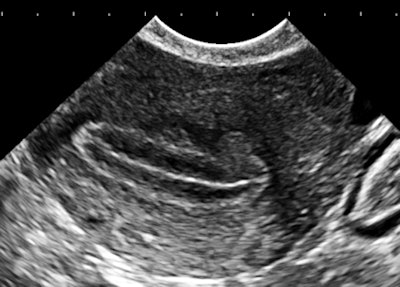

| Magnification view of a portion of the right kidney of a 32-year-old woman with ductal carcinoma in situ (DCIS) and a bicornuate uterus. All images courtesy of Dr. Jason Birnholz. |

The finding is a very early form of medullary sponge kidney. The vascular arcades at the corticomedullary borders (normal) and the punctuate nonshadowing reflectors within the pyramids are visible due to noise suppression.

The information content of this image is high. Frequency components are predominantly high, which can be seen here in the 2D fast Fourier transform (FFT) of this same image.